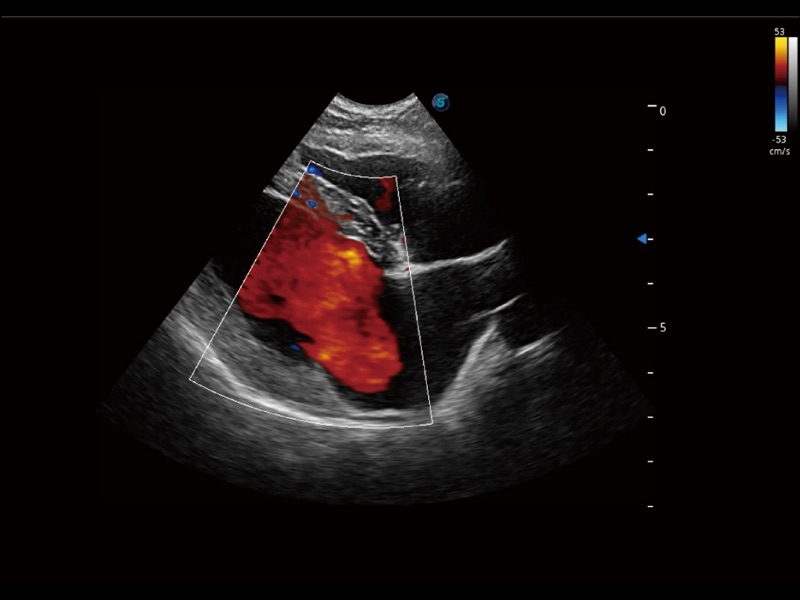

通過創(chuàng)新的 Matrix E自適應(yīng)濾波器和超長時(shí)間域算法,極大提升超低速微細(xì)血流的檢出能力,同時(shí)更精準(zhǔn)地濾除軟組織和噪聲信號,為獸用醫(yī)生提供以往無法通過常規(guī)血流獲得的疾病診斷信息。

通過色彩血流和實(shí)時(shí)寬景相結(jié)合,可觀察到完整的靜脈或動脈的血流,方便醫(yī)生檢查。實(shí)時(shí)掃查過程中,如有任何操作失誤也可以很容易地進(jìn)行回掃擦除,而不會中斷掃查。

采用紅、橙、黃、綠、青、藍(lán)、紫這七種肉眼最為敏感的色彩,直觀地顯示組織內(nèi)血流灌注的時(shí)間先后信息,更精準(zhǔn)捕捉血流灌注走行細(xì)節(jié)。